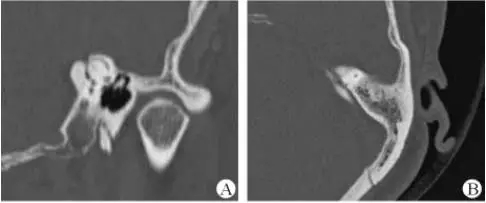

醫生若懷疑此病將會安排內耳CT掃描。在大多數案例中,一旦此病被耳鼻喉科醫生或其它聽力健康專家確診,則可實行手術治療。外科手術風險包含聽力損失以及神經損傷;重建及復原需內耳的治療以及大腦的重塑。